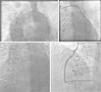

Case reportsCase AA 74-year-old male had a history of hypertension and CAD with previous CABG, including left internal mammary (LIMA) to left anterior descending (LAD), saphenous vein graft (SVG) to posterolateral (PL) branch, SVG to first diagonal and SVG to posterior descending artery (PDA). He developed chest pain and presented with an inferior wall STEMI. Per a previous angiogram performed at another hospital, his SVG to PDA graft was considered chronically occluded. Emergent cardiac catheterization revealed significant native multivessel disease. The LIMA-LAD, SVG-PL and SVG-diagonal grafts were all widely patent. The SVG to PDA graft was totally occluded proximally with fresh thrombi (Figure 1A). As this graft had an ostial stent protruding about 5 mm into the aorta, cannulation was difficult, and required a multipurpose guide catheter. Intravascular ultrasound was used to properly characterize this lesion, then aspiration thrombectomy of a fresh thrombus was successfully performed (Figure 1B) followed by placement of a drug-eluting stent. In retrospect, this graft had been considered totally occluded on a previous angiogram, probably due to the difficulty of cannulation. Proper engagement of the graft this time spared the patient significant myocardial damage that might have resulted from not intervening on this culprit artery.